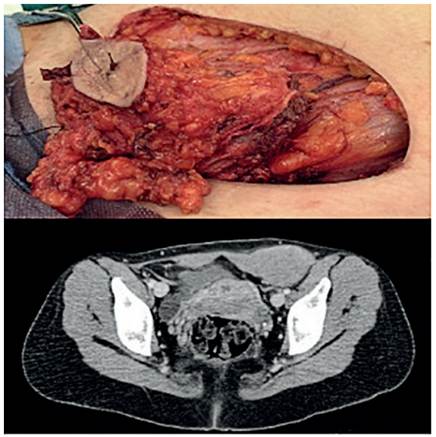

Las pacientes fueron mujeres jóvenes, con edades comprendidas entre los 22 y los 34 años (ME 29,6 años). La principal causa de consulta fue la aparición de una masa en la pared abdominal, localizadas sobre una cicatriz quirúrgica tipo Pfannenstiel, por cesárea en dos pacientes y por resección de un disgerminoma en la otra paciente, con dolor a la movilización. Sólo una de ellas consumía anticonceptivos orales. El diagnóstico se realizó mediante tomografía computarizada y biopsia con aguja gruesa guiada por ecografía (Tabla 1).

En todas las pacientes el tratamiento se realizó mediante una resección quirúrgica amplia con márgenes libres, que incluyó músculo y aponeurosis, respetando el peritoneo y la vascularización epigástrica. El defecto se reconstruyó con doble capa de malla de polipropileno en dos pacientes y en un caso con malla simple. Ninguna de las pacientes recibió tratamiento adyuvante.

Como se realizó en nuestras pacientes, el tratamiento de elección es la resección quirúrgica con márgenes libres, incluyendo la extirpación de las estructuras circundantes a la tumoración, para evitar las recidivas. No obstante, la cirugía presenta una alta tasa de recidiva, cercana al 25 %, llegando hasta el 60 % en algunas series. Debido al gran tamaño de las masas, la reparación primaria del defecto quirúrgico no suele ser posible, por lo que en muchos casos es necesario la realización de colgajos o la utilización de material protésico o mallas 9.